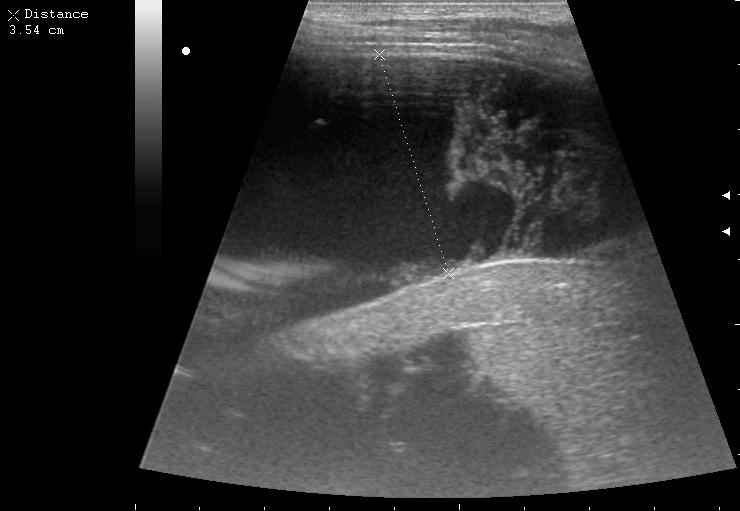

железный дрын вошел в правую подвздошную область, остановился в капсуле печени.

наезд большой черной Прады на маленькую (13кг) 5-летнюю девочку.

получает Медаксон, рабочая версия - изменение желчного пузыря вследствии травмы (шепотом - рекомендация хирургу сменить антибиотик)

сегодня был селезёночный день.